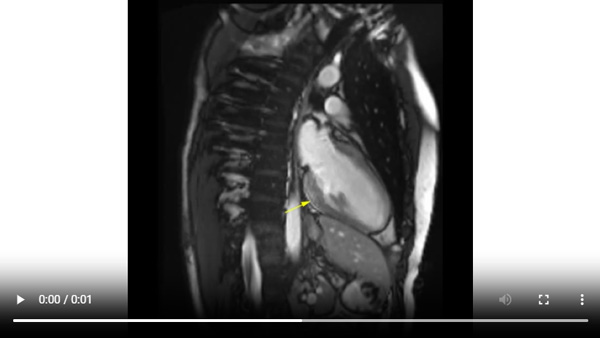

Figure 4A : Séquence de rehaussement tardif - Coupes petit-axe

Figure 4B : Séquence de rehaussement tardif - Coupes long-axes

Présence d’une zone de rehaussement tardif sous-épicardique aux niveaux inféro-latéro-basal et inféro-basal (zones blanches, flèches jaunes) comparée au reste du myocarde (noir).

Retenez le dogme selon lequel le muscle cardiaque sain apparaît toujours « noir » sur les séquences de rehaussement tardif.

Visualisation d’un rehaussement myocardique systolique à prédominance sous-épicardique sur les cinés long-axe (2 cavités et 3 cavités) acquises après injection de gadolinium. C’est un signe assez évocateur d’œdème myocardique, qui est souvent retrouvé en cas de myocardite aiguë.